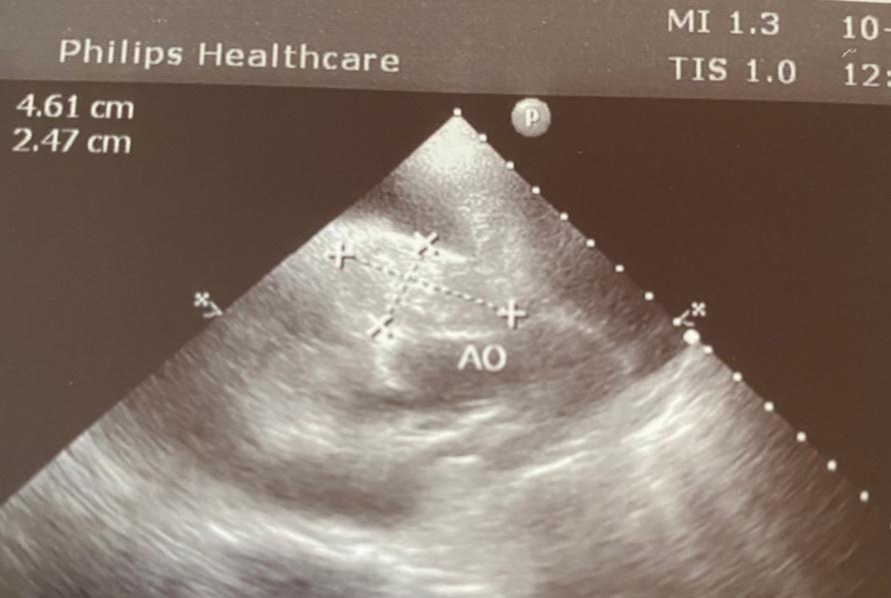

W dzisiejszym poście omówimy jedną z takich chorób: nowotwór serca psa. Bezpośredni asumpt do takich refleksji dała nam konsultacyjna wizyta kardiologiczna jednego pacjenta. Był to 9 letni owczarek niemiecki, który na początku marca poczuł się źle. Właściciel zauważył spadek aktywności i jego lekarz prowadzący skierował czworonoga do nas na konsultacje kardiologiczną ze względu na płyn w jamie opłucnej i otrzewnej. Diagnozą okazał się rozległy nowotwór serca. Jego rokowanie niestety było złe. Jak widać w tym przypadku nawet szybka reakcja nie zawsze pomoże naszym pupilom, ale aby dać im szansę badajmy nasze czworonogi i reagujmy, tak szybko, jak tylko to możliwe.

Pomocne bywają badania radiograficzne, echokardiograficzne i angiograficzne, rezonans i tomografia. Niewiele wnoszą natomiast badania krwi. Ostateczne postawienie diagnozy możliwe jest po dokonaniu biopsji mięśnia sercowego. Jednak najczęściej diagnoza zostaje postawiona dzięki pośmiertnym badaniu histopatologicznemu serca.